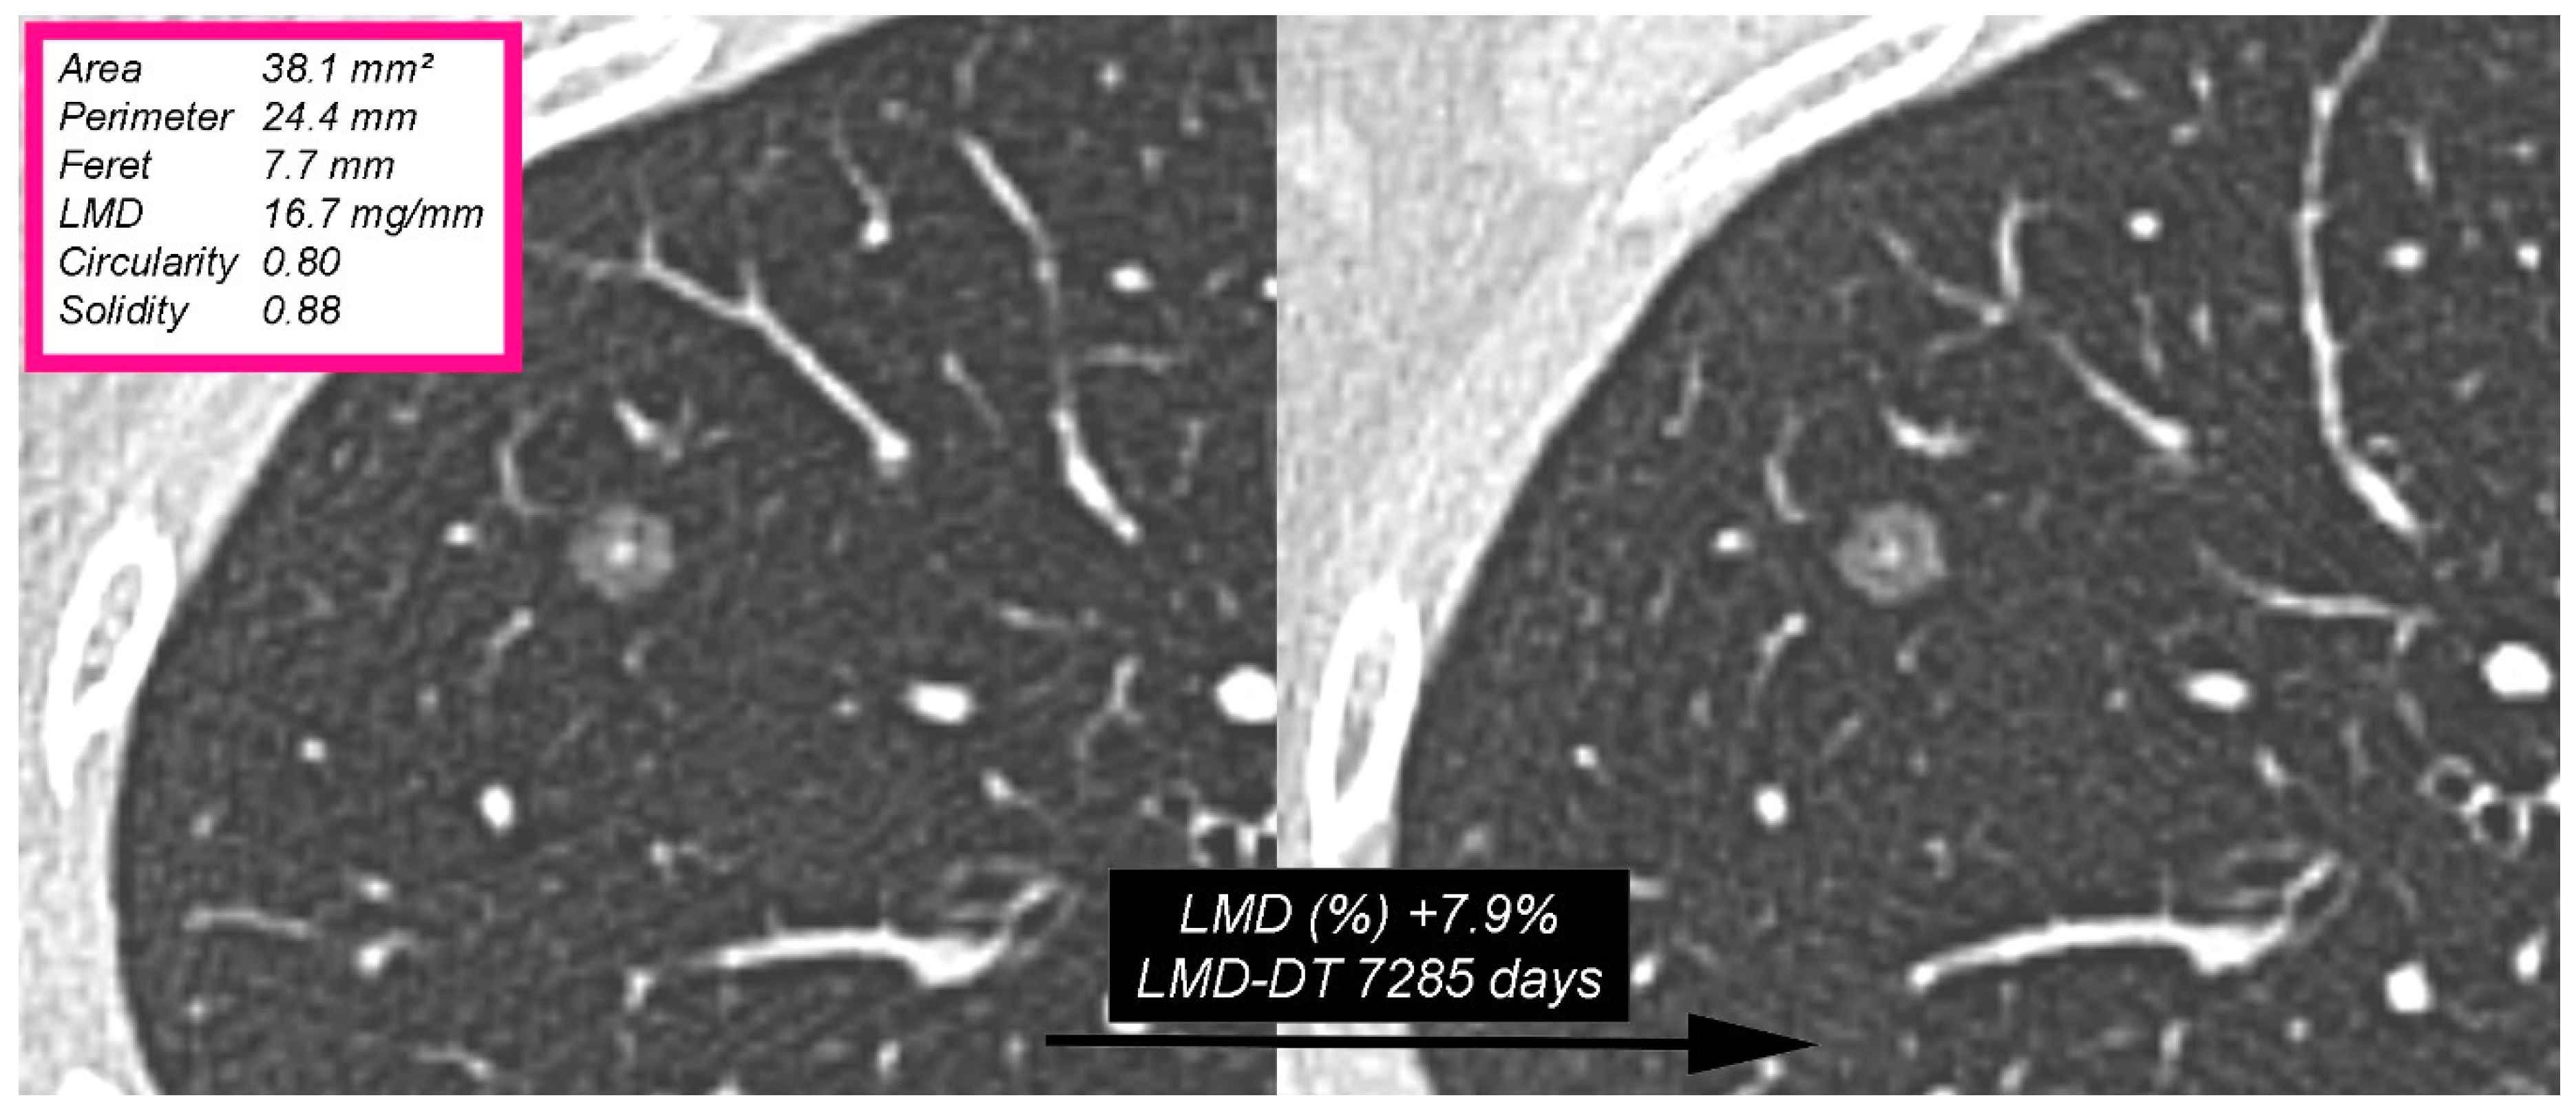

| LMD (mg/mm) | 31.4 (20–43.5) | −0.326 | 0.021 |

| Circularity | 0.64 (0.52–0.75) | 0.519 | <0.001 |

| Solidity | 0.81 (0.74–0.87) | 0.457 | <0.001 |

| LMD (mg/mm) | 35.3 (22.8–44.2) | 21.6 (18.1–30) | 0.007 |

| Circularity | 0.59 (0.46–0.66) | 0.76 (0.64–0.82) | <0.001 |

| Solidity | 0.78 (0.71–0.84) | 0.88 (0.82–0.93) | 0.001 |